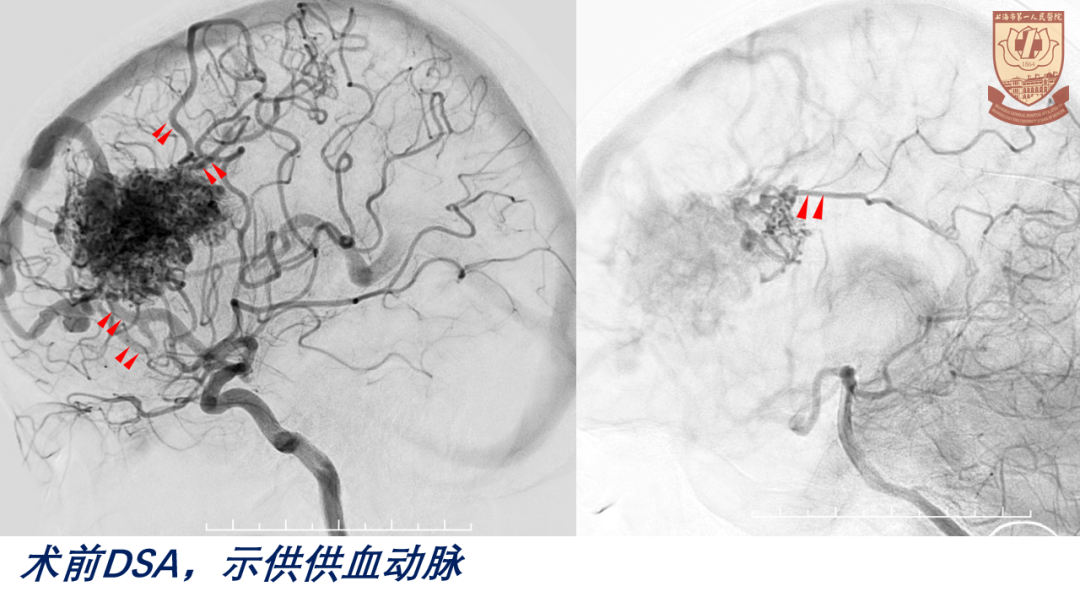

CTA、DSA:左侧额叶AVM

nidus构筑

供血动脉:三组

前:左侧A3、胼缘动脉

后:大脑中动脉分支、脉络膜后动脉(后胼周动脉)

外:白质穿支动脉